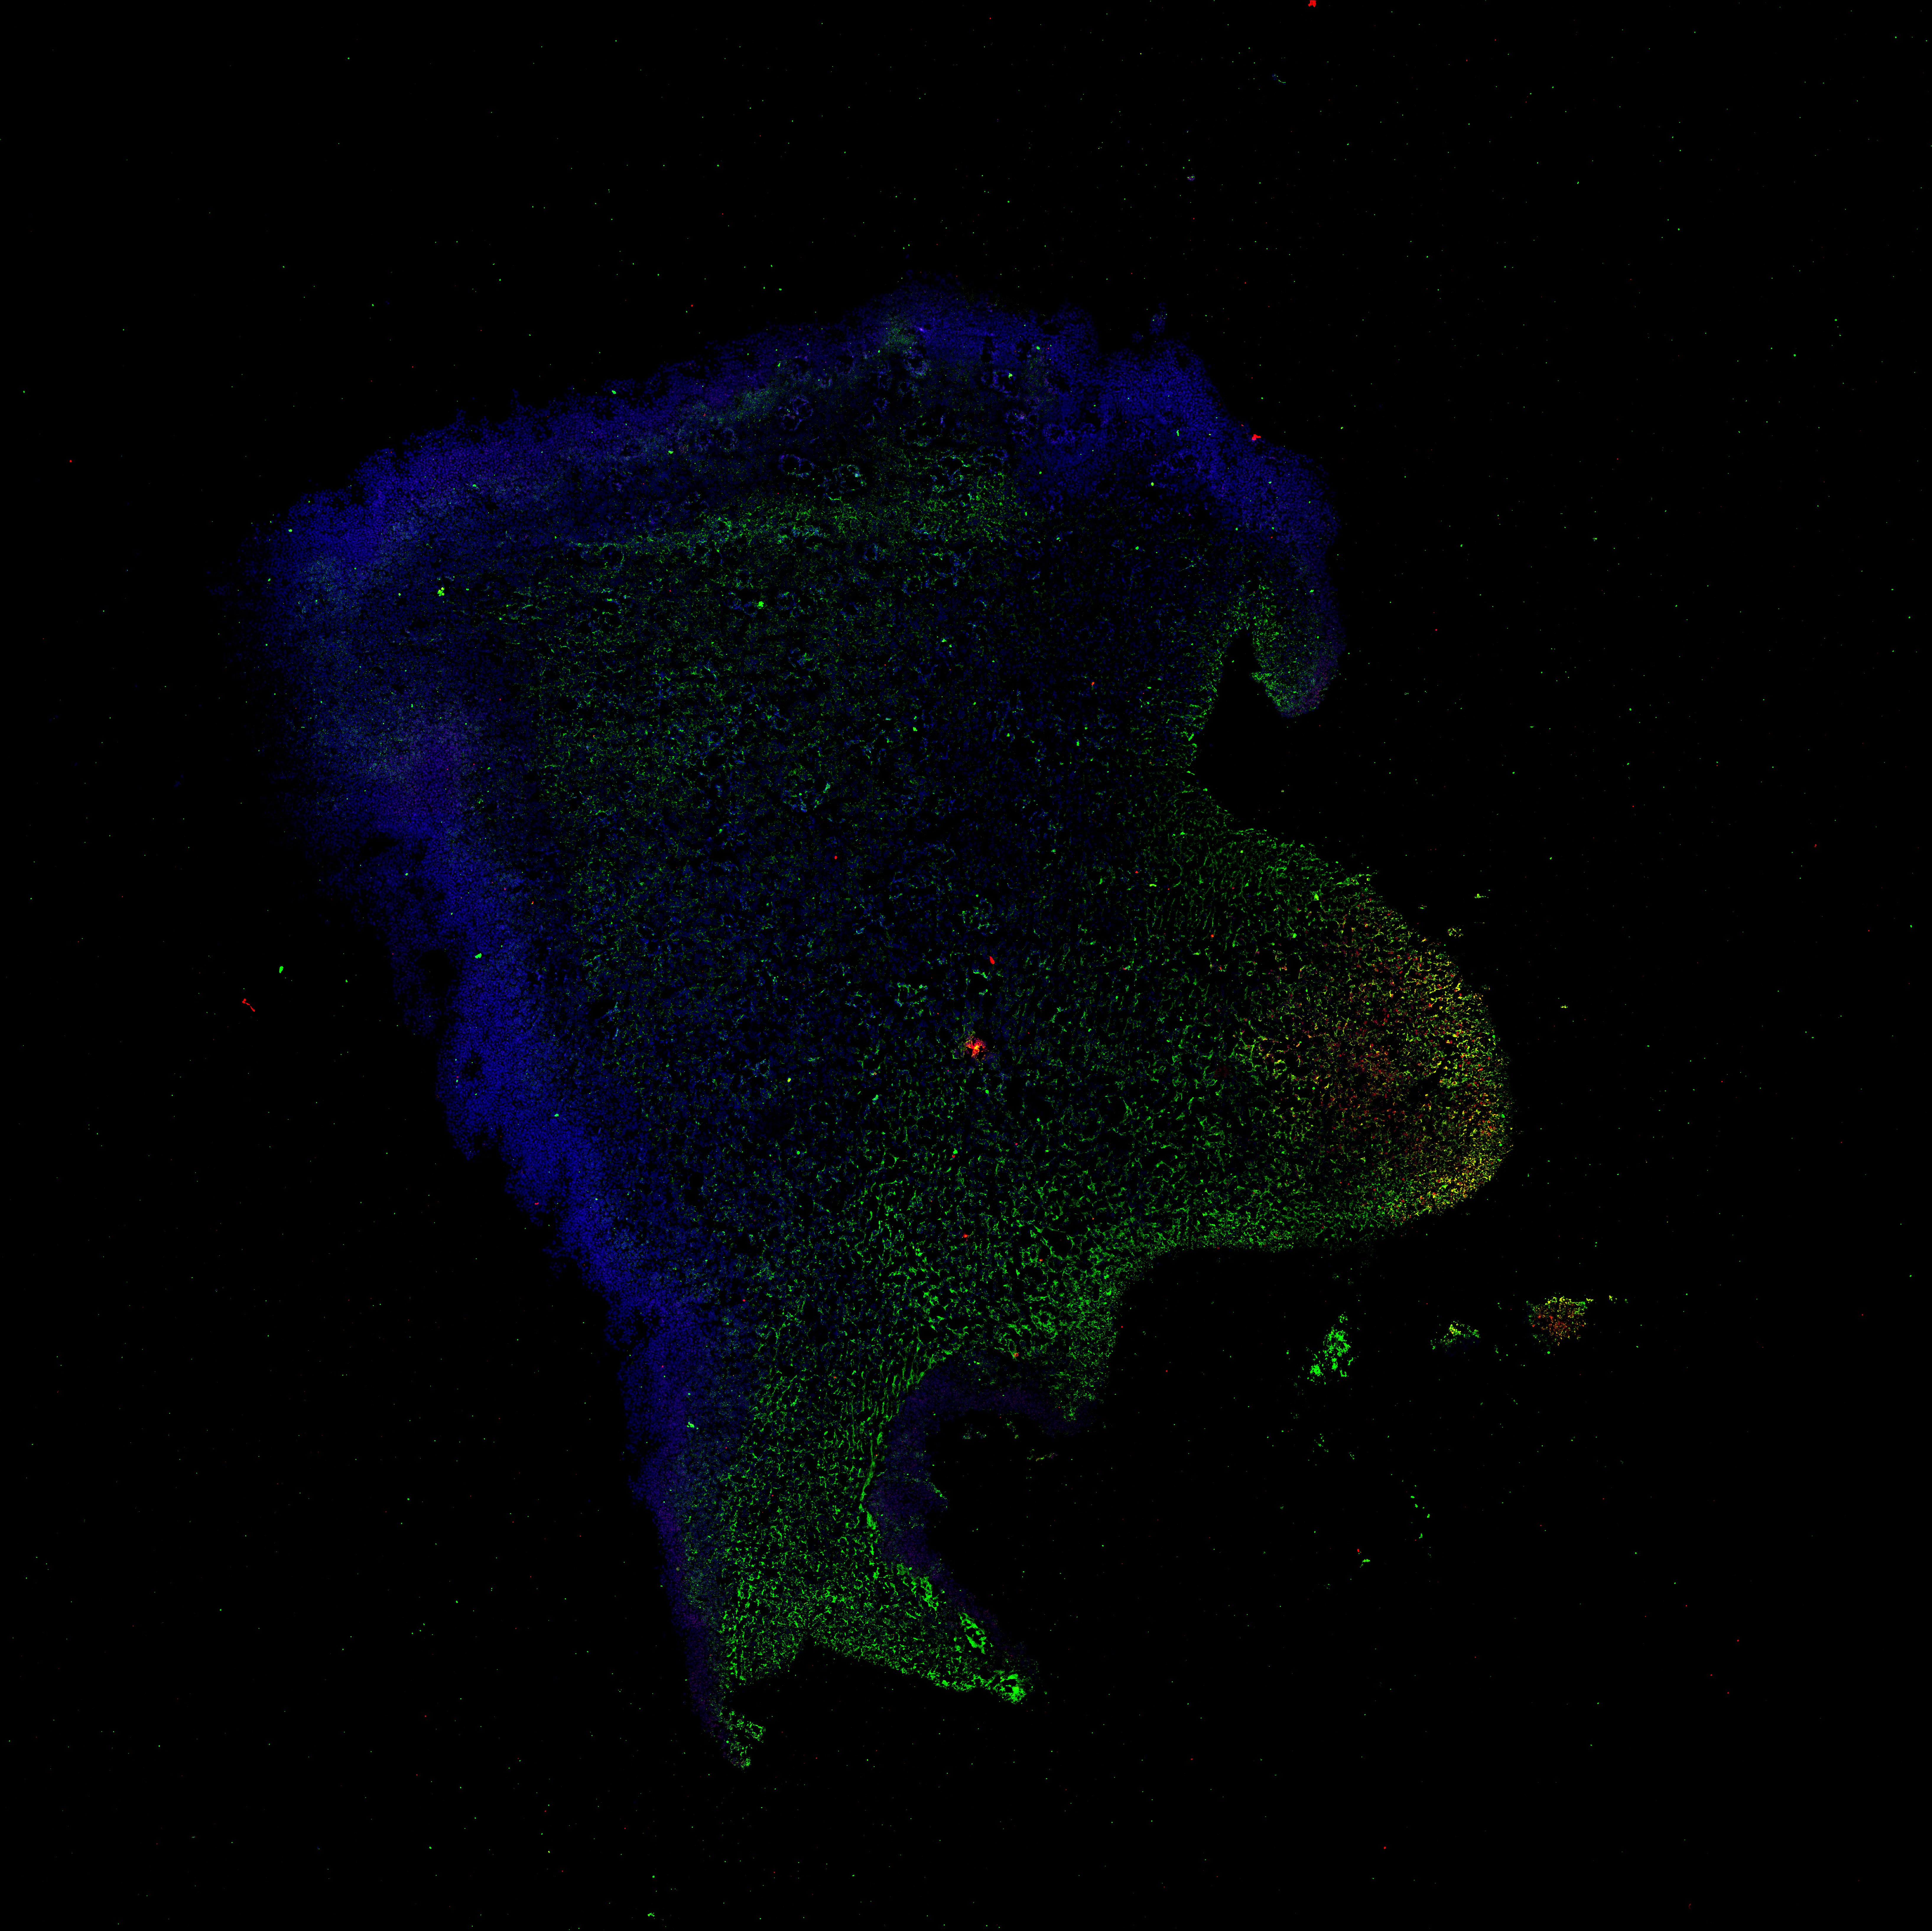

An anatomical analysis of the developing human midbrain from 6 post-conceptional weeks (PCW) to 22 PCW reveals increased tissue complexity, characterized by the emergence of dopaminergic nuclei, as highlighted by immunofluorescence analysis for tyrosine hydroxylase (TH).

Merged

6PCW human midbrain